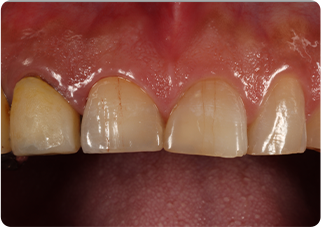

セラミッククラウン症例①

術前

仮歯

技工物

術後

| 主訴 | 見た目を綺麗にしてほしい |

|---|---|

| 治療期間/回数 | 3ヵ月、5回 |

| 価格(税込) | 363,000円(税込) |

| リスク・副作用 | セラミック破損の可能性 |

| ポイント | 自然な色、形となるようにオーダーメイドでセラミックを盛ってクラウンを作製した。 |